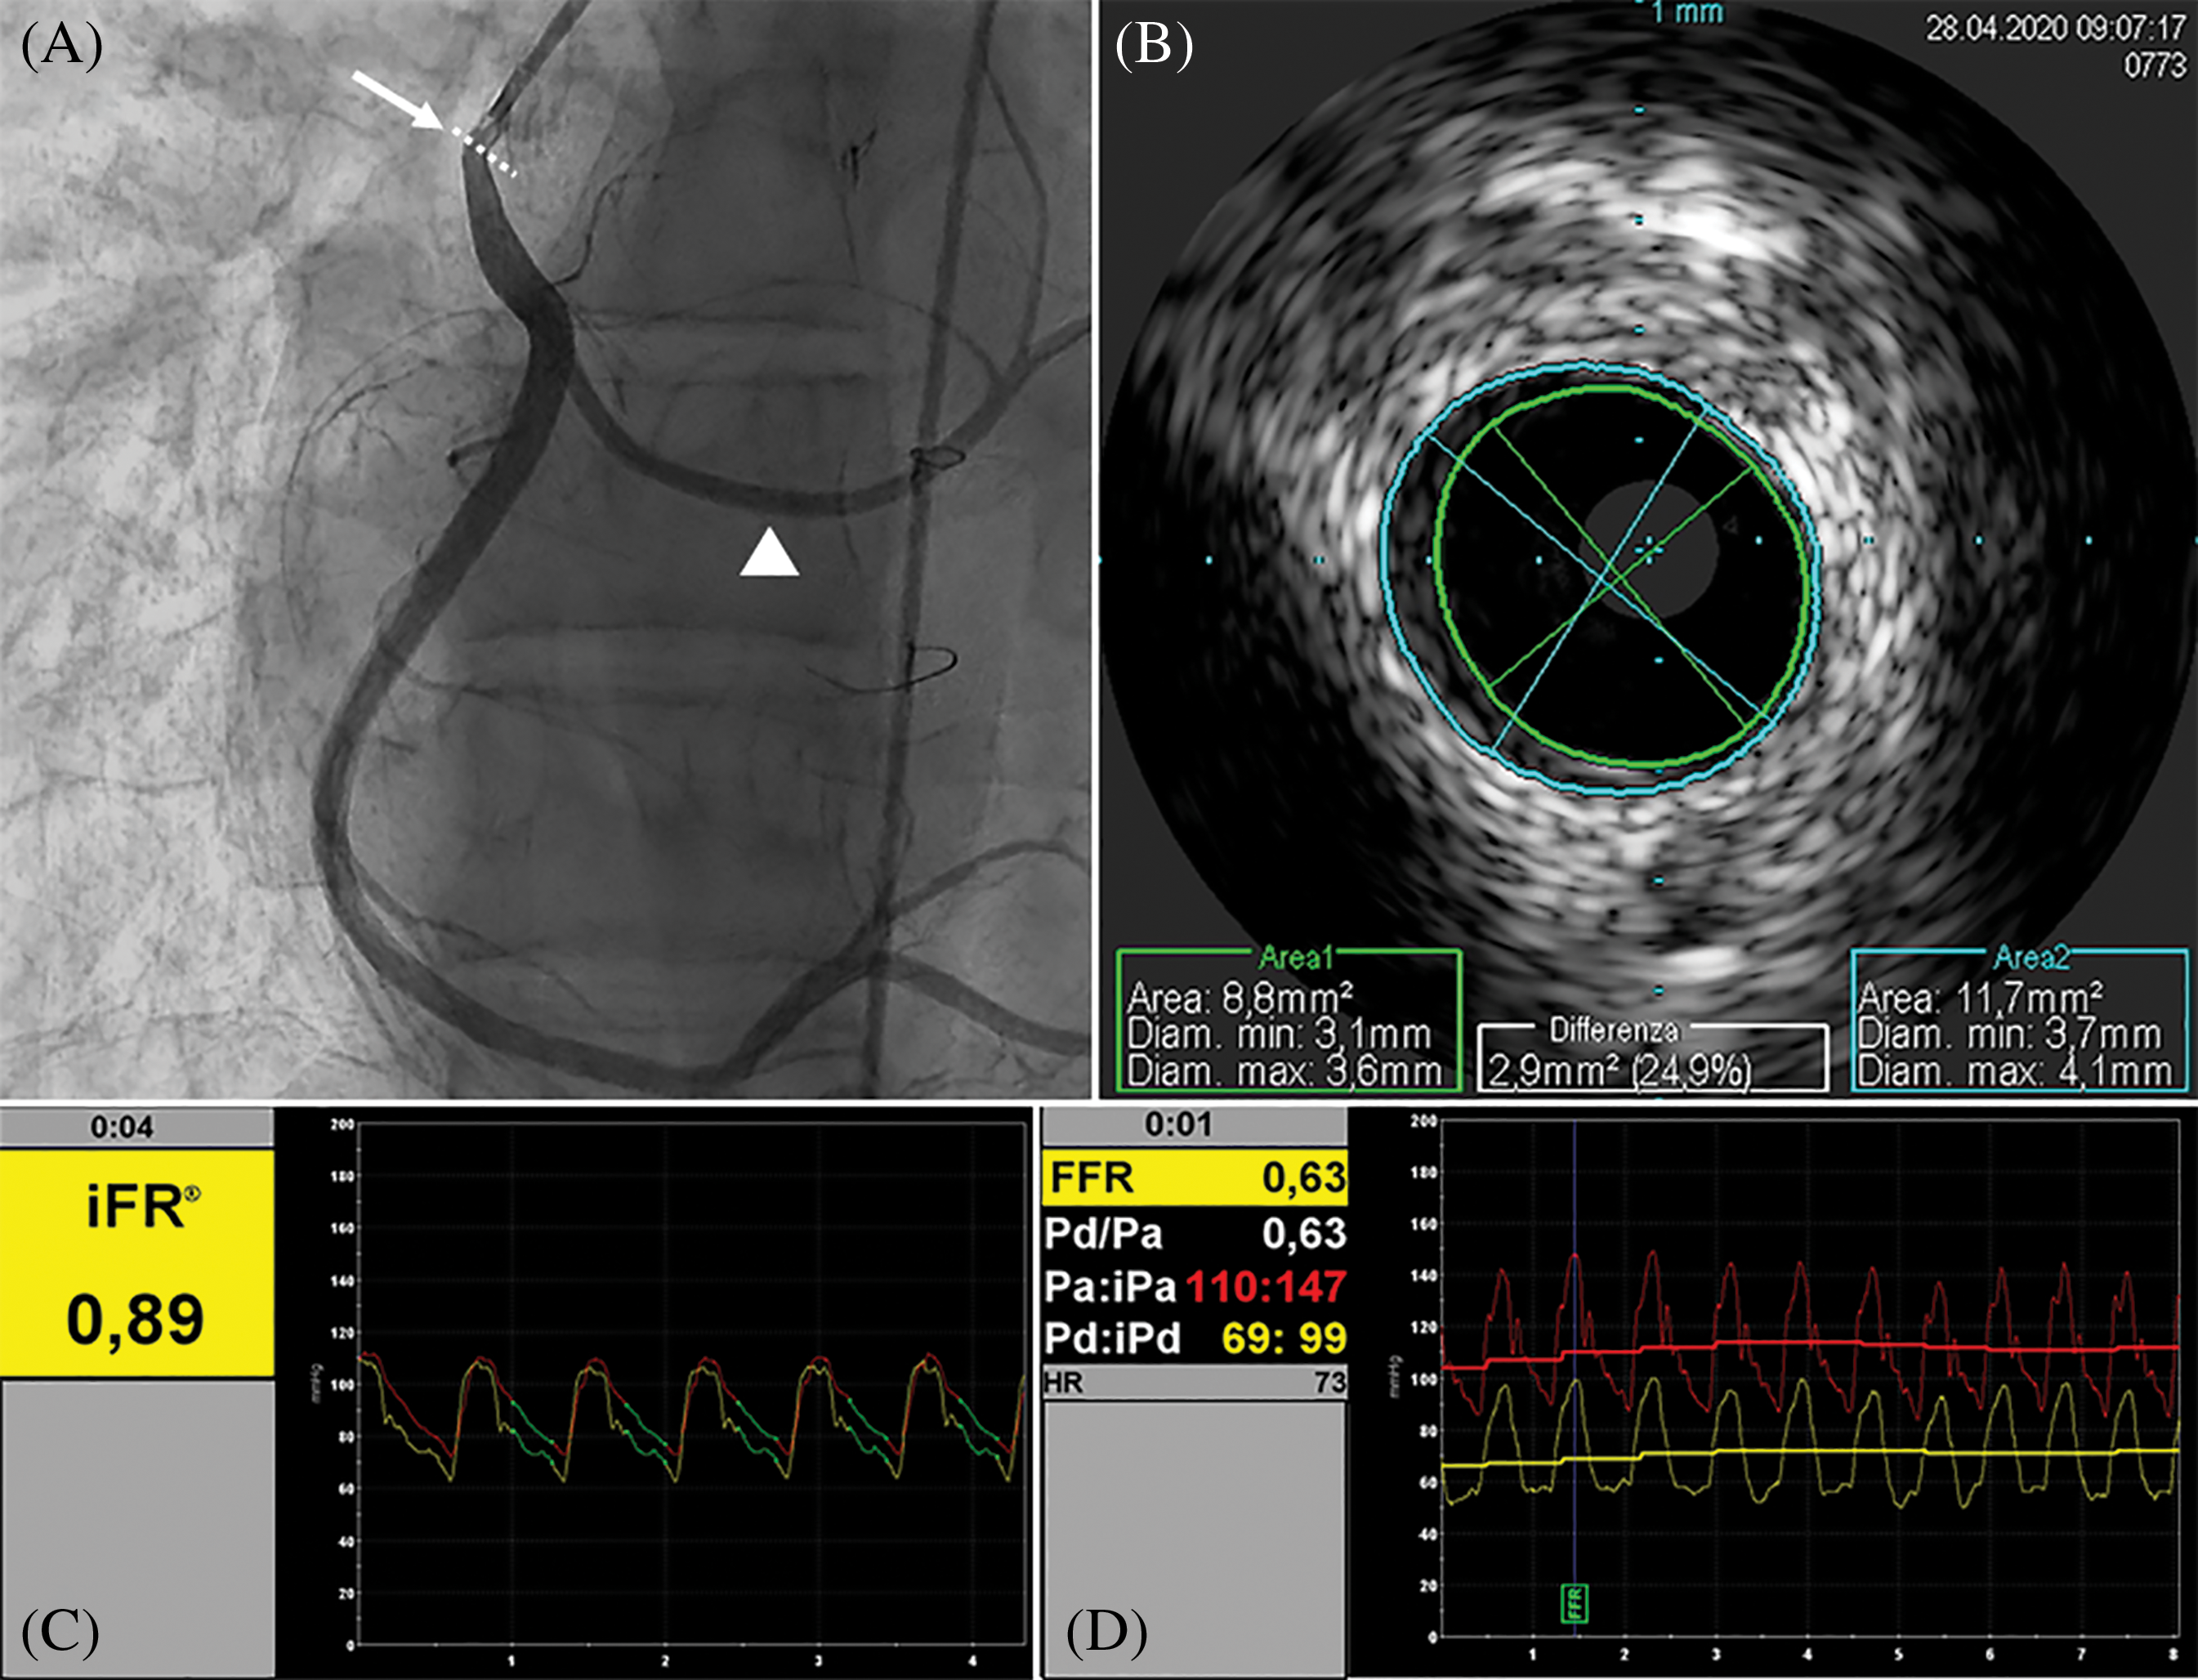

A 17-year-old male, body weight 73 kg, height 190 cm, was electively admitted in our Hospital to undergo invasive coronary angiogram. He had a past history of D-TGA, ventricular septal defect (VSD) and anomalous origin of the left circumflex coronary artery (LCx) from the right coronary artery (RCA). At the age of 2 weeks, he underwent surgical repair with ASO, LeCompte maneuver, coronary artery translocation and VSD closure. As per local protocol to assess coronary anatomy after ASO, at 10 years of age he was referred for elective coronary angiography, showing a 50% lumen stenosis at the origin of RCA. Subsequently, he underwent myocardial perfusion scintigraphy (SPECT) at rest and under pharmacological stress with adenosine infusion, which demonstrated a small perfusion defect of the mid-segment of the anterior wall under stress. Unfortunately, given the presence of right bundle branch block on the electrocardiogram (EKG), repolarization abnormalities assessment during the stress were not reliable for myocardial ischemia diagnosis. Considering the un-correlation of the two diagnostic exams regarding ischemic territory and the absence of symptoms, the decision made was to not treat the stenosis and to follow-up the patient yearly with electrocardiogram (EKG), transthoracic echocardiogram (TTE), and exercise-stress testing. At 17 years of age he repeated a SPECT at rest and under physical exercise stress test, which showed hypo-perfusion of mid- and basal segments of both anterior and inferior wall under stress. TTE showed preserved left ventricle ejection fraction (LVEF biplane 55%), reduced LV global longitudinal strain (GLS −15%), more evident in the inferior and posterior septum wall, and preserved right ventricular (RV) function. Following multidisciplinary team discussion, the patient was admitted for elective coronary angiogram. On admission patient was preloaded with 600 mg of clopidogrel PO. Through femoral artery access, selective angiogram showed dominant RCA with a 50% ostial stenosis (Fig. 1A). IV unfractioned heparin 5000 UI was administered. Thereafter, intravascular ultrasound (IVUS) was employed to better characterize the stenosis from the anatomical standpoint. IVUS (Eagle Eye Platinum ST®, Philips Volcano,) showed mild reduction of RCA ostium minimal lumen area (MLA 8.8 mm2) with mild and eccentric neo-intimal proliferation, in absence of clear atherosclerotic plaque (Fig. 1B). Subsequently, we performed a functional analysis of the stenotic segment using a coronary pressure wire (Verrata Plus®, Philips Volcano). Firstly, we measured the instantaneous wave-free ratio (iFR) which resulted 0.89, falling in the so-called “grey zone”, and then the fractional flow reserve (FFR) pre- and post-adenosine induced (400 mcg intracoronary) hyperaemia which was 0.89 and 0.63 respectively (Figs. 1C and 1D). Given the FFR positive result, 250 mg of aspirin IV were given, and then a 4 × 15 mm zotarolimus eluting stent (Resolute Onyx®, Medtronic, CA, USA) was implanted at 18 Atm. Post dilation of the stent was performed with a 4 × 8 mm non-compliant balloon (NC Euphora®, Medtronic, CA, USA) with excellent angiographic result (Fig. 2A). Post-stenting IVUS evaluation displayed good apposition of the stent struts to the coronary wall and minimal protrusion (<1 mm) in the aortic root (Fig. 2B). Finally, functional analysis was repeated, showing an FFR value post-adenosine infusion of 0.83 (Figs. 2C and 2D). Patient was transferred back to the ward and initiated on aspirin 100 mg OD and clopidogrel 75 mg OD the following day. Pre-discharge TTE demonstrated preserved LVEF and mild improvement of GLS to −16.5%. He was discharged home on day 1 after PCI in good condition with a 12-month plan of dual antiplatelet therapy (DAPT).

Figure 1: Basal assessment. A, Angiography showing intermediate ostial stenosis of RCA (arrow), anomalous origin of LCx (head arrow) from the RCA. B, IVUS evaluation of the stenotic segment, showing mild eccentric neointimal hyperplasia causing mild stenosis and a MLA of 8.8 mm2. C, iFR resulting 0.89, falling in the so-called “grey zone”, and then in D the FFR after intracoronary infusion of adenosine significantly reduced (0.63). Right coronary artery (RCA). Left circumflex artery (LCx). Intravascular ultrasound (IVUS). Minimal lumen area (MLA). Instantaneous wave-free ratio (iFR). Fractional flow reserve (FFR)